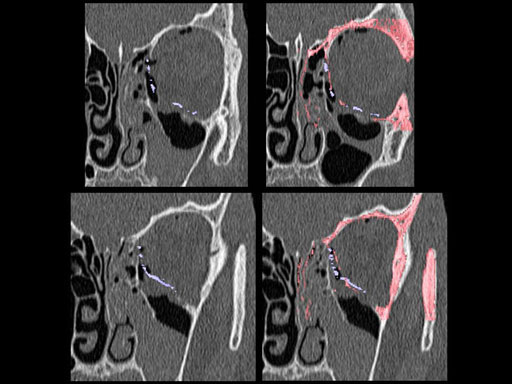

Unlike the existing two-dimensional mesh implants, the geometry of the new preformed plates will be adequate to match the individual anatomic situation of the patient in almost any case. However, the mesh parts can be individually adjusted if necessary. In these cases the solid part in the central posterior area needs to remain untouched. Areas of the orbit that do not require a bridging can be spared out by trimming the implant along the designated cutting lines in the height of the medial wall and/or length of the orbital floor area. The lateral anterior part of the plate is intentionally pre-bent higher than the orbital rim anatomy to allow free plate movement during plate positioning.

The Preformed Orbital Plates are indicated for trauma repair and reconstruction of fractures of the orbital floor, medial orbital wall or combined fractures of floor and medial wall. It should be noted that in three-wall fractures where the lateral wall is also involved, a second orbital implant, ( i. e. the mesh plate) must be used in addition to the pre-formed orbital plate.

Implant placement according to the orbital landmarks

1 Orbital rim, 2 Inferior orbital fissure, 3 Posterior orbital ledge, 4 Transition between the medial wall and orbital floor, 5 Optic canal, 6 Lacrimal fossa